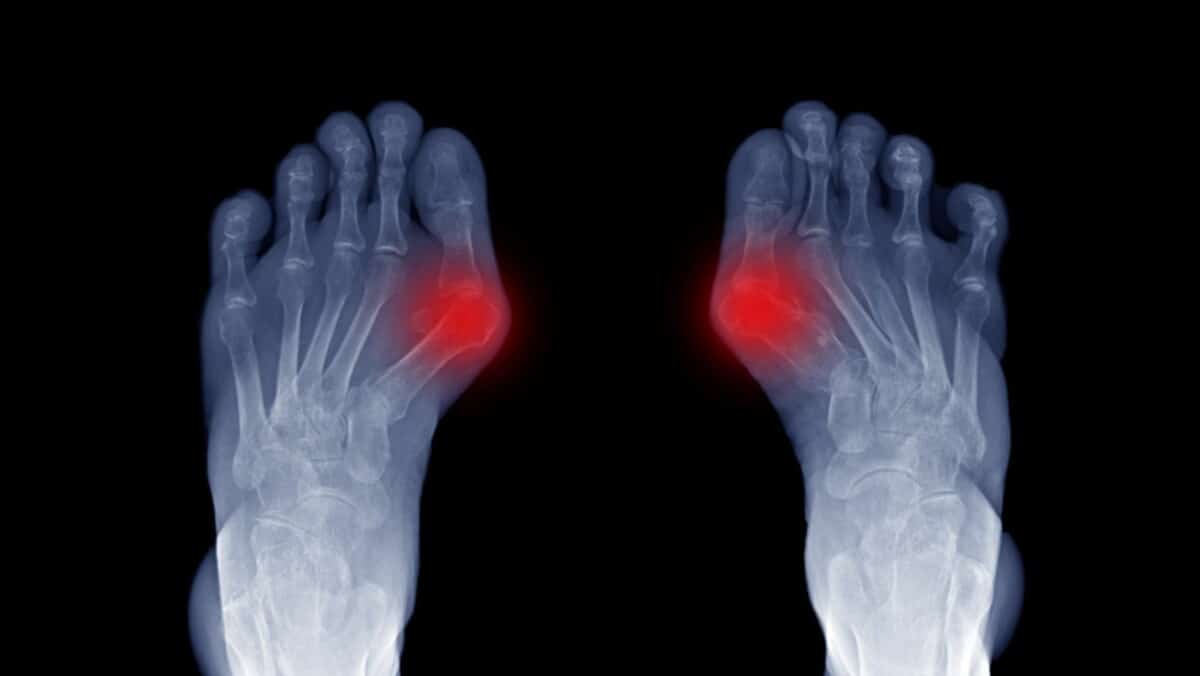

Big Toe Arthritis Treatment . Learn about the causes, symptoms, and treatments of hallux rigidus, the most common arthritic condition in the foot. It causes pain and stiffness. Because it is a progressive condition, it will eventually affect the ability to bend the big toe. Oa of the toe can’t be cured, but you do have some options for managing the pain and swelling: Hallux rigidus is a type of arthritis affecting the mtp joint at the base of the big toe. If you are experiencing arthritic pain of the big toe, consult an orthopedic or arthritis specialist to discuss a diagnosis. Also known as big toe arthritis, hallux rigidus is a. What’s the best way to manage oa of the big toe (hallux rigidus)? In this video, we discuss big toe arthritis and the advanced treatment options available at ufai.